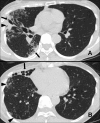

We report the first case of Segniliparus rotundus pneumonia in an adult with non-cystic fibrosis bronchiectasis. All isolates were identified as S. rotundus by 16S rRNA gene sequencing and rpoB PCR-restriction analysis. Antibiotic therapy with clarithromycin and ciprofloxacin for 2 months improved the patient's condition and achieved successful sputum conversion.